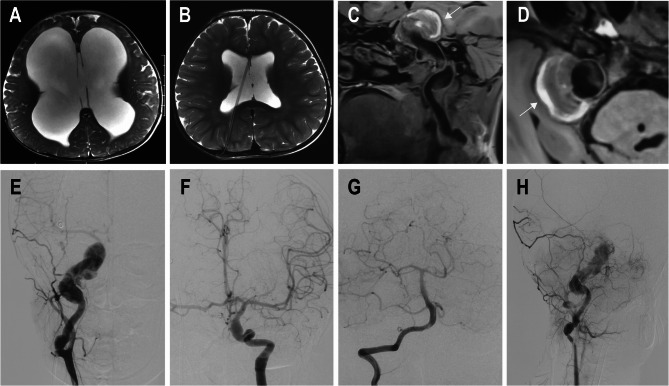

Case presentation: In the first case, a 15-year-old boy initially presented in July 2020 with recurrent mild nausea and vomiting. He was diagnosed with left internal carotid artery (ICA) occlusion secondary to a giant fusiform aneurysm, along with a cerebellar arachnoid cyst. The patient received conservative treatment but did not adhere to the recommendation for regular follow-up. In August 2023, he developed hydrocephalus and severe brainstem compression caused by VBD. Ventriculoperitoneal (V-P) shunting failed to prevent rapid clinical deterioration, which eventually led to fatal intracranial hemorrhage. The second case involved a 9-year-old boy who initially presented in June 2013 with hydrocephalus and underwent V-P shunting. In June 2020, he was diagnosed with right ICA dolichoectasia during an evaluation for neck discomfort and subsequently underwent ligation of the right ICA. In March 2022, he experienced an acute onset of altered consciousness, and neuroimaging confirmed brainstem compression due to VBD. Considering the high anesthetic risk and the limited potential benefit of further surgical intervention, treatment was withdrawn, and the patient ultimately died of brainstem infarction.